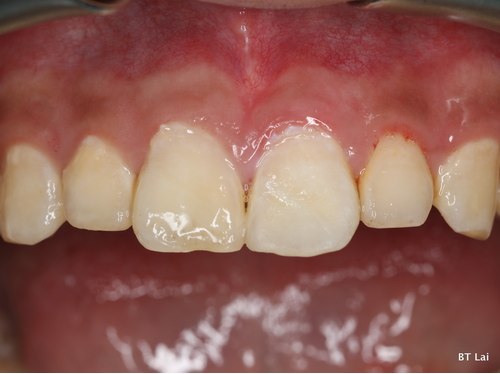

7歲孩童小松是在一年半前不小心把上顎新萌發的恆齒撞斷,經急診醫師會診根管治療科賴博堂主任接手以活髓治療。現在的小松雖然偶爾會因咬到堅硬的食物而使黏上去的斷片掉落,需再重新黏上之外,整顆牙仍保留恆齒成長潛能。

左圖:7歲孩童小松撞斷後一年半後牙齒成長狀況。(賴博堂提供)